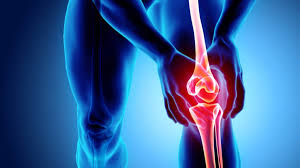

살아가는데 다리가 아프다면 생활하는데 큰 지장을 주게 됩니다. 아래다리와 허벅지 사이에 있는 무릎은 여러가지 원인으로도 인해 큰 통증이 발생할 수 있습니다. 하지만 무릎통증 원인을 알고 개선해 나간다면 무릎통증을 줄이는데 많은 도움이 될 것입니다. 그렇다면 오늘은 무릎통증 원인에 어떤 것이 있는지 알아보도록 하겠습니다.

무릎이란 무릎관절은 정강이뼈와 넙다리뼈를 잇는 다리 관절로서 다리를 구부리면 돌출되는 부위를 이야기합니다. 무릎은 인대, 근육, 뼈 등으로 구성되어 있습니다. 걷기,웅크리기, 뛰기와 같은 고난도 동작을 수행하는데 도움을 주는 부위입니다. 그렇기 때문에 평소에 우리들의 무릎은 많이 압력을 받고 있습니다. 평소에 무릎이 자주 아프다면 병원에 가셔서 간단한 검사를 받아보시는 것이 좋습니다.

무릎통증 원인